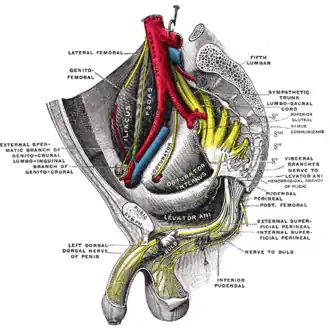

Sacral plexus of the right side.

Sacral plexus of the right side. -